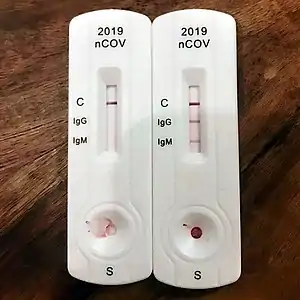

COVID-19-testning kan identificere SARS-CoV-2-virussen og inkluderer metoder, der både påviser tilstedeværelsen af selve virussen (RT-PCR[note 1]) og metoder, der påviser antistoffer dannet som reaktion på infektion.

Højre: Eksempel på resultater for en sådan test. Viser for antistofferne IgM og IgG

Påvisning af antistoffer (jf. serologi, vedr. serum[note 2]) kan bruges både til diagnose og til populationsovervågning. Antistofprøver viser, hvor mange mennesker der har haft sygdommen, inklusive dem, hvis symptomer var mindre eller som var asymptomatiske. En nøjagtig dødelighed af sygdommen og niveauet for flokimmunitet i befolkningen kan bestemmes ud fra resultaterne af denne test. Varigheden og effektiviteten af dette immunrespons er imidlertid stadig uklar.[1]